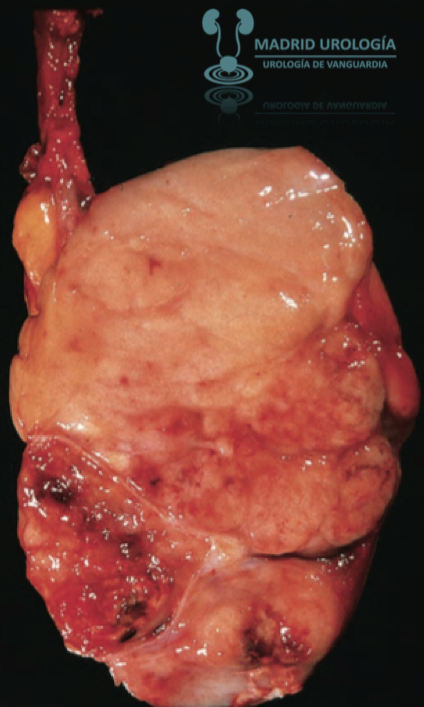

![]() |

| Seminoma de apariencia cefaloidea difusa y con focos hemorrágicos. |